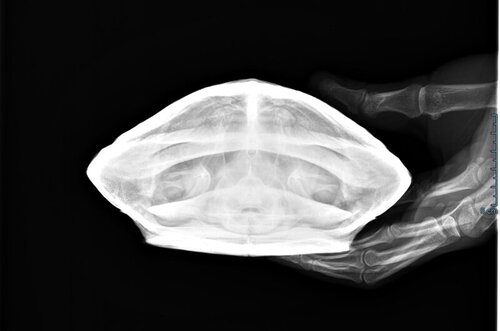

Даша17 Ваше имя: Дарья Локация: Россия, Зеленоград Опубликовано: 14 августа 2022 Автор Опубликовано: 14 августа 2022 @moth здравствуйте! Мы все таки съездили на приём к Дарье Мазепе, сделали рентген, яиц и никаких съеденных посторонних предметов нет, но увеличены яичники, еще немного увеличена печень (от обжорства), и еще незначительная компрессия лёгких (но нам объяснили, что это из-за раздувшихся яичников, так как никаких больше нет потологий). Пока голодовка две недели, потом давать 1 раз в неделю корм и снова потом уже 2 раза, и наблюдение, и рентген через 2-3 месяца, чтоб посмотреть яичники. В общем, спасибо вам за рекомендацию! Доктор замечательная @moth единственное, что вот хотела спросить, если яичники увеличены, и например, яйца не разовьются в этом году, то они сами сдуются, или это может быть опасно?